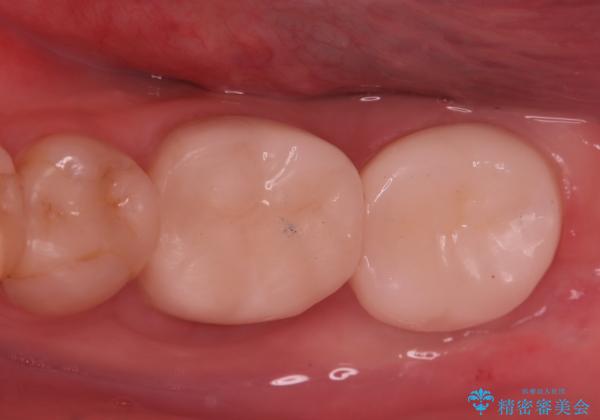

【根管治療】他院でインプラントの提案があった。奥歯が痛い。

- 左下の奥歯の治療の継続を主訴に来院されました。

1週間ほど前に、自発痛の既往があり他院で応急処置を行ってもらったとのことです。

そこでは、抜歯してインプラントの治療を提案されたとのことです。

レントゲンや口腔内所見にて以下のような説明ののち、患者様が保存を希望されたため、当院では根管治療~オールセラミッククラウンにて修復処置を行いました。痛みも消えて、経過良好です。